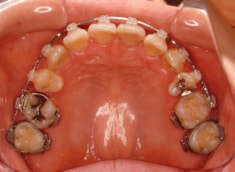

治療開始から約1年2ヶ月後